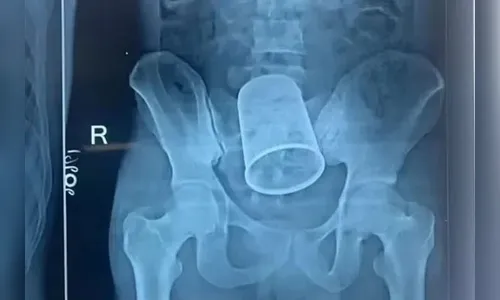

Autor Exames de imagem mostraram o objeto dentro do corpo do jovem - Foto: Reprodução

Um homem de 22 anos da cidade de Bettiah, na Índia, foi submetido a uma cirurgia de emergência para retirar um copo de metal do corpo. O caso aconteceu na terça-feira (4). De acordo com a imprensa local, o objeto, de 14 centímetros de comprimento e 7 de diâmetro, foi introduzido pelo próprio paciente através do ânus durante uma bebedeira.

Conforme os médicos do Patna Medical College Hospital, o paciente chegou ao pronto socorro às 4 horas da madrugada com fortes dores e sangramento no reto. Exames de imagem mostraram o objeto dentro do corpo do jovem.